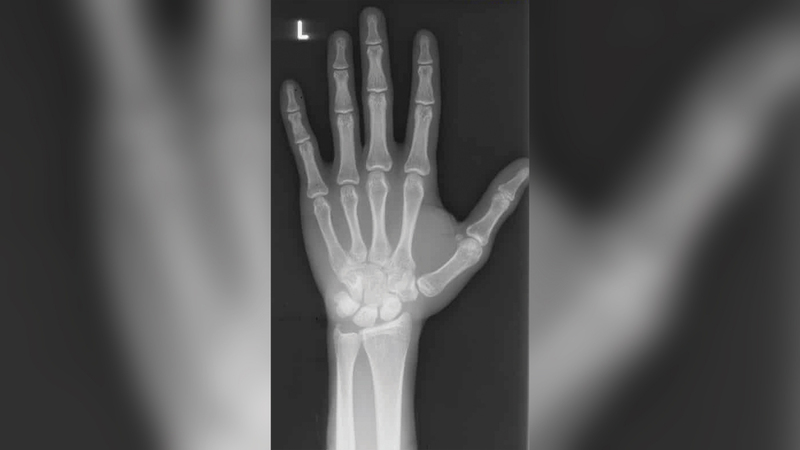

ولكن بدلاً من ذلك، اعتمدت الشرطة على استخدام الأشعة السينية لمعرفة أعمارهم، وتم استخدام الأشعة السينية لاستنتاج أن الأولاد من المحتمل أن يكونوا بالغين، وعلى هذا النحو وجهت إليهم الشرطة تلك التهم. وقد أقر جميع الأولاد ما عدا واحداً بالذنب.

ولكن فيما بعد ثبت عدم مصداقية هذه التقنية تماماً. الأسبوع الماضي، ألغت محكمة الاستئناف بغرب أستراليا إدانة رودي عثمان، حمزة جوجو، محمد مالينغ، مايكيل هوسا، عثمان آري وفاندي، الذين مثلهم مكتب المحاماة كين كوش وشركاه. ووجدت المحكمة أن «خطأً جسيماً في تطبيق العدالة قد حدث». وقررت المحكمة أنه بغض النظر عن استخدام الأشعة السينية على الرسغ لمعرفة أعمارهم، فإن الأولاد الستة «لا يجب اتهامهم كأشخاص بالغين» كما قررت المحكمة أنه لا اختصاص لمحكمة مقاطعة غرب أستراليا في النظر في قضاياهم. ووجدت أن «حجة الأدلة المتاحة المتبقية، فيما يتعلق بتاريخ ميلاد كل مستأنف، لا يمكن أن تدعم النتيجة التي تفيد بأن أياً من المستأنفين، في وقت تقديم الطلب، كان يبلغ من العمر 18 عاماً أو أكثر من ذلك».

وقالت المحكمة إن المدعين العامين في الكومنولث قد أقروا الآن بأن اعتمادهم السابق على دليل الأشعة السينية للمعصم «يثير شكاً صريحاً حول نزاهة كل اعتراف بالذنب وبشأن نزاهة كل قرار بعدم تحديد عمر المستأنف». وتقر المحكمة بعدم وجود دليل موثوق به عندما أدين كل مستأنف وحُكم عليه بأنه يبلغ من العمر 18 عاماً أو يزيد على ذلك.

وتكشف الوثائق المرفقة بقضية الأولاد أن كلاً من الشرطة وكبار الشخصيات الحكومية كانوا يعرفون قبل سجن الصبية أن هناك شكوكاً حول دقة الاتهام. وتُظهر المستندات التي اطلعت عليها صحيفة الغارديان أن ضابط تحقيق في بعض القضايا كان متورطاً في محاكمة مماثلة بشكل ملحوظ قبل ثماني سنوات، واستمعت خلالها المحكمة إلى أن استخدام دليل الأشعة السينية للمعصم لتحديد العمر كان عرضة للخطأ و«ليس دقيقاً للغاية».

وتكشف إحاطة قسم الهجرة الداخلية في يونيو 2010 أن الحكومة قد تم تحذيرها بشكل مباشر من عدم موثوقية هذه التقنية. وحدثت هذه الإحاطة قبل فترة طويلة من إدانة خمسة من الأطفال الستة والحكم عليهم، بعد استخلاص تقارير الأشعة السينية.

وحذر الإيجاز الحكومة من أن الأشعة السينية للمعصم معرضة للخطأ، وأشار إلى إرشادات المملكة المتحدة التي حذرت من استخدامها لتحديد العمر، والتي قالت: «تمت مناقشة مسألة ما إذا كان يمكن تحديد العمر الزمني من تقدير عمر العظام، والجواب هو أنه لا يمكن ذلك». بعد حوالي ثلاث سنوات وشكاوى متعددة حول احتجاز الأطفال في سجون البالغين، تم الإفراج عنهم وإعادتهم إلى ديارهم.